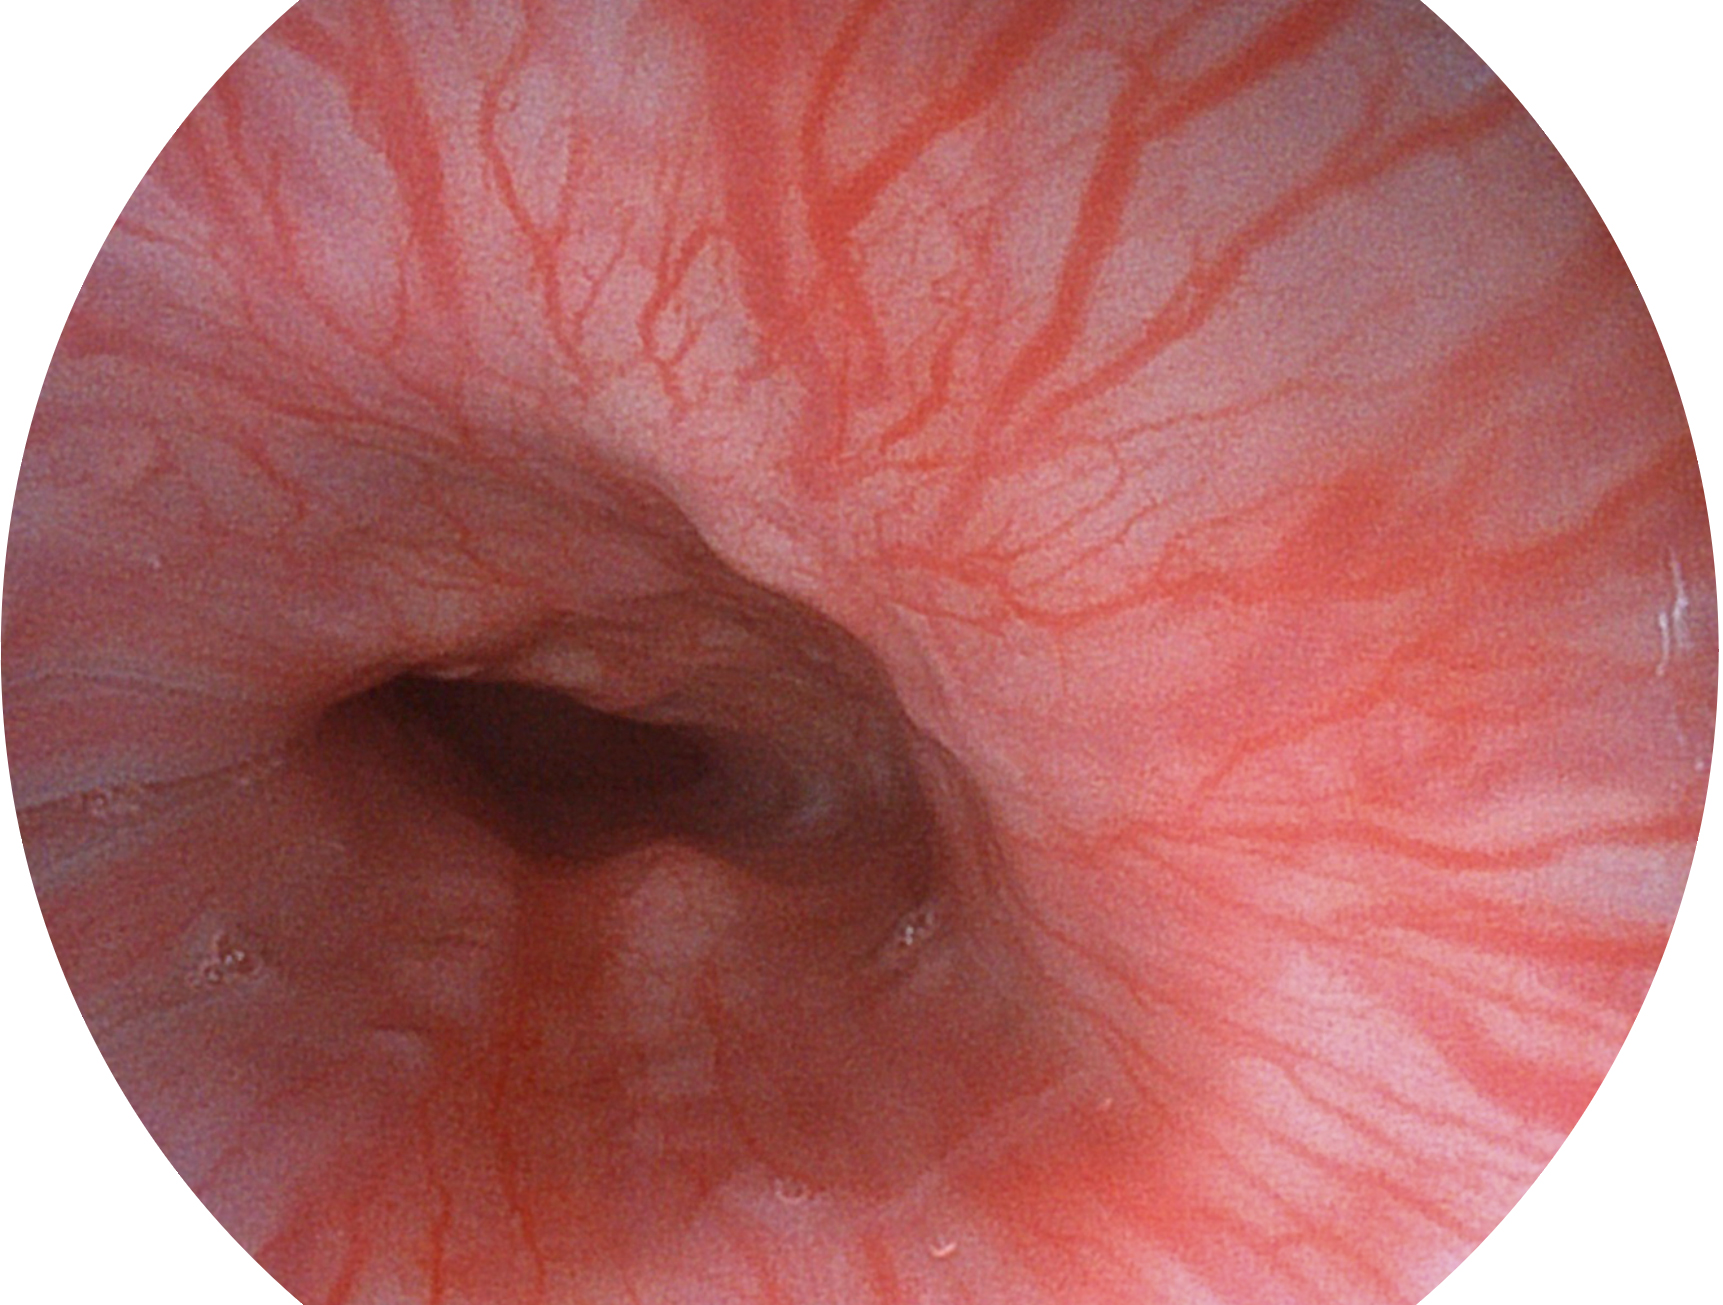

百老汇电子游戏官网新开发的内镜染色技术,主要是基于多波长LED 光源的开发,VLS-55Q 四波长LED 光源是由四个不同颜色的LED光按照相应照明模式所规定的特定发光比例进行合束后形成,合束后形成的照明光的光谱由红光、绿光、蓝光及蓝紫光这四个不同的波段范围构成。具有更高光谱自由度,通过光谱比例的控制,实现了聚谱成像技术,英文全称为“Spectral Focused Imaging, SFI”,缩写为“SFI”和光电复合染色成像技术,英文全称为“Versatile Intelligent Staining Technology, VIST”,缩写为“VIST”。